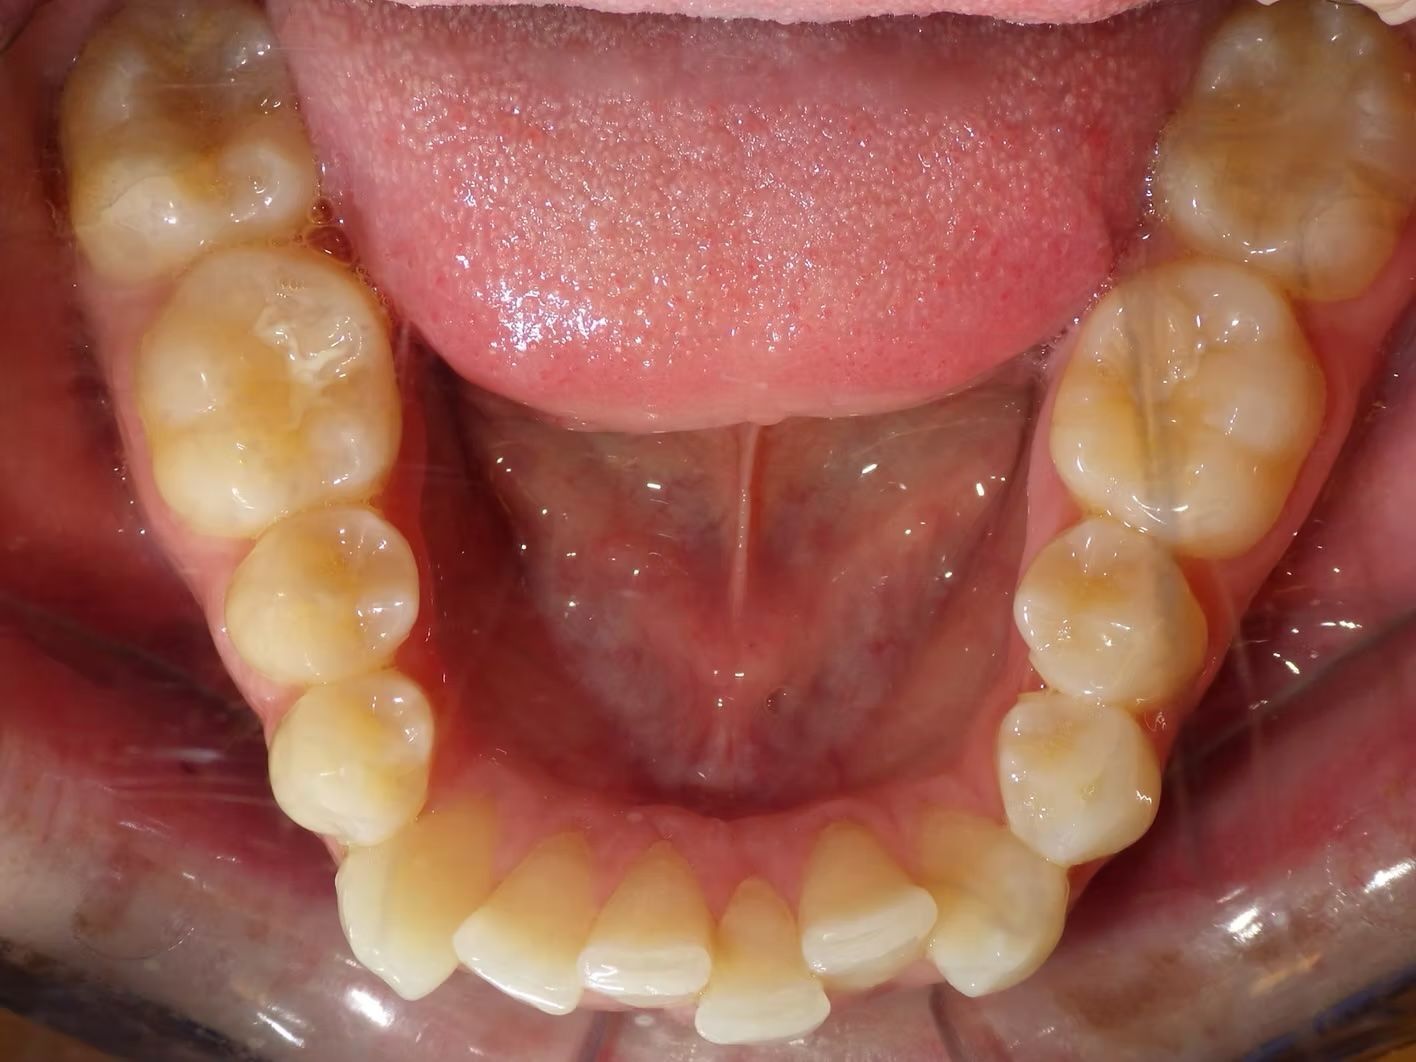

IAN

Ian came to the office because his lower teeth were crowded and he had an anterior cross bite. With traditional braces we resolved the crowding and aligned the teeth without causing flaring of the incisors and giving him a handsome smile. The treatment lasted 18 months and the final photos are at a 2 year follow up when we made him a new clear retainer.